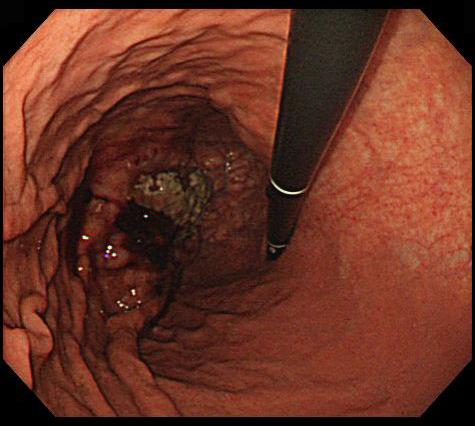

症例提示(所在地,施設名等): 福岡県・ 九州医療センター (平賀聖久先生からの提供症例)

疾患(病理主体)の分類悪性リンパ系腫瘍/悪性リンパ腫

部位(臓器別)胃(部位)/2つ以上

検査方法内視鏡

病変の最大径(ミリ)40以上

腫瘍の深達度s(a)

多発腫瘍(同一臓器)有(同時性)